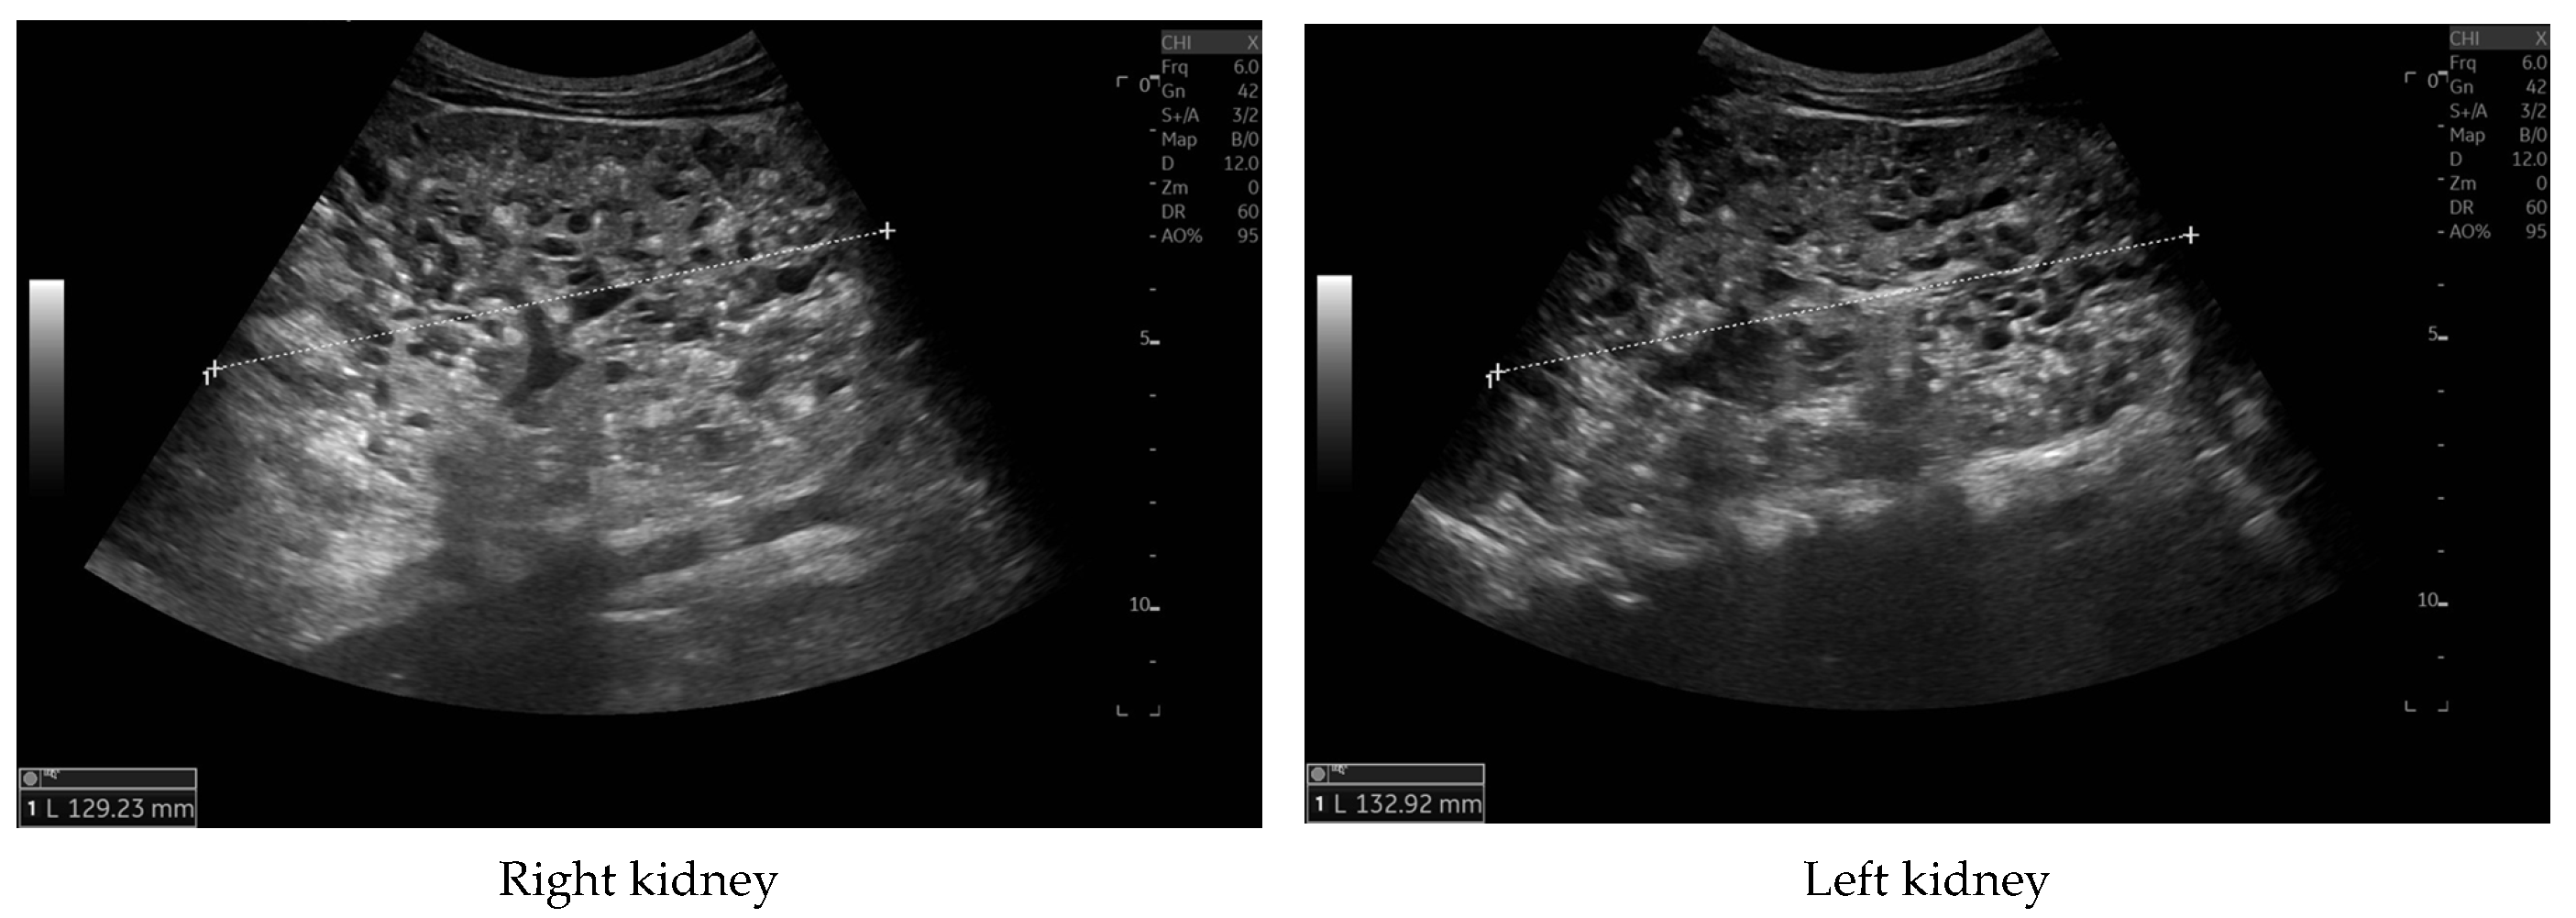

At 4 months of age, the boy was admitted to the hospital due to a hypertensive crisis (BP 162/128 mmHg). Chest X-ray demonstrated cardiomegaly, and echocardiography (ECHO) showed a significant left ventricular hypertrophy and impaired contractility. Abdominal US detected increased kidneys length (right: 101 mm (z-score 8.72); left: 90 mm (z-score 6.59)), with increased echogenicity and loss of corticomedullary differentiation, as well as numerous cysts 5–6 mm in diameter. The liver was enlarged with increased echogenicity with cysts 6–8 mm in diameter (Figure 1 and Figure 2). Doppler US demonstrated high-resistance intrarenal blood flow (RI: 0.75–0.84). Laboratory tests showed microcytic anemia, renal function was assessed as serum creatinine, the glomerular filtration rate (GFR) was estimated according to the Schwartz formula, and liver function was all normal. The boy received multi-drug therapy to control hypertension and heart failure. ECHO, performed after 6 months, was correct.

Figure 1. Ultrasonography of kidneys at the age of 4 months (enlarged kidneys with multiple cysts).